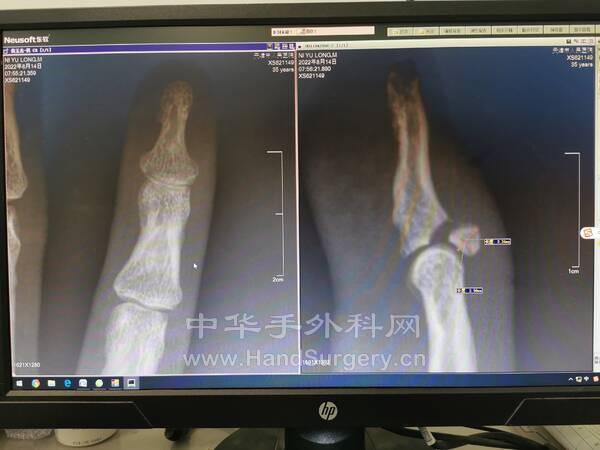

骨块大小2.56mm×2.34mm×3mm

计划术中看能否直接用针头穿骨块固定

但是术中发现骨块过小